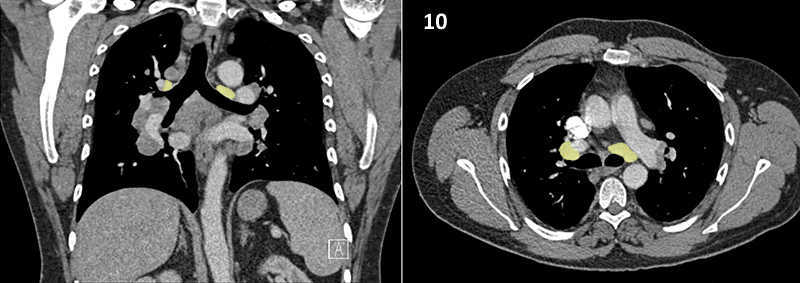

Nodal zones and stations according to the International Association for the Study of Lung Cancer (IASLC) node map.

Table (above): Nodal zones and stations according to the International Association for the Study of Lung Cancer (IASLC) node map. (Source: 1,2) *Depends on the side of the tumour.